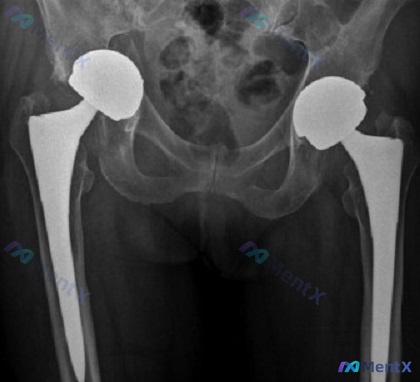

整理了一个挺有警示意义的关节置换后病例,看似简单的跌倒痛,影像还报了「位置良好」,但结合病史逻辑推演下来风险极高。 病例基本信息 - 年龄/性别:72岁女性 - 背景:2年前接受非骨水泥型右全髋关节置换术(注:影像显示是双侧置换,但本次主诉为右侧) - 主诉:跌倒后右髋疼痛 影像初步描述(阅片+报告...